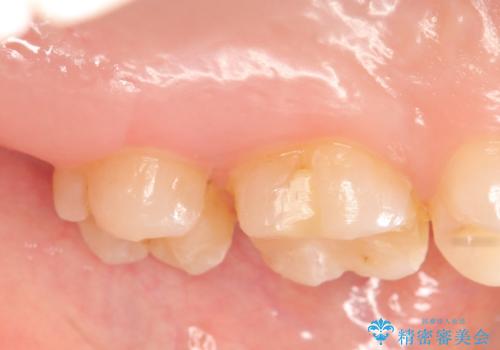

左上7近心の虫歯は歯茎より深く、歯茎を下げるため歯周外科を行いました。

術後歯肉の回復を待ち、左下6、7ともにセラミックインレーによる修復を行いました。

当院のセラミックインレーはemaxという強度と審美性に優れた材料を使用しています。

またプレス方式でインレーを製作しているため、削り出しで製作するCADCAMより優れた適合性も持ち合わせており、虫歯が再発しにくい修復物です。